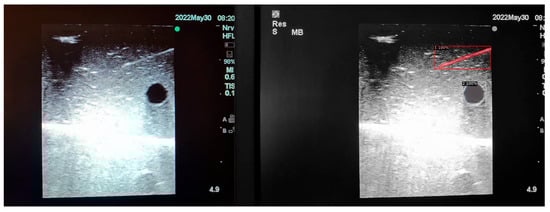

Moreover, false positives can arise where structures that are not present are falsely identified as present. This can occur in certain mediums like Phantom C (Smelleze), where the echogenic needle track mark (overlayed in yellow) left behind is misidentified as a needle alongside the actual needle (overlayed in grey) as shown in Figure 8.

Figure 8. Original and result images of falsely identified needle.